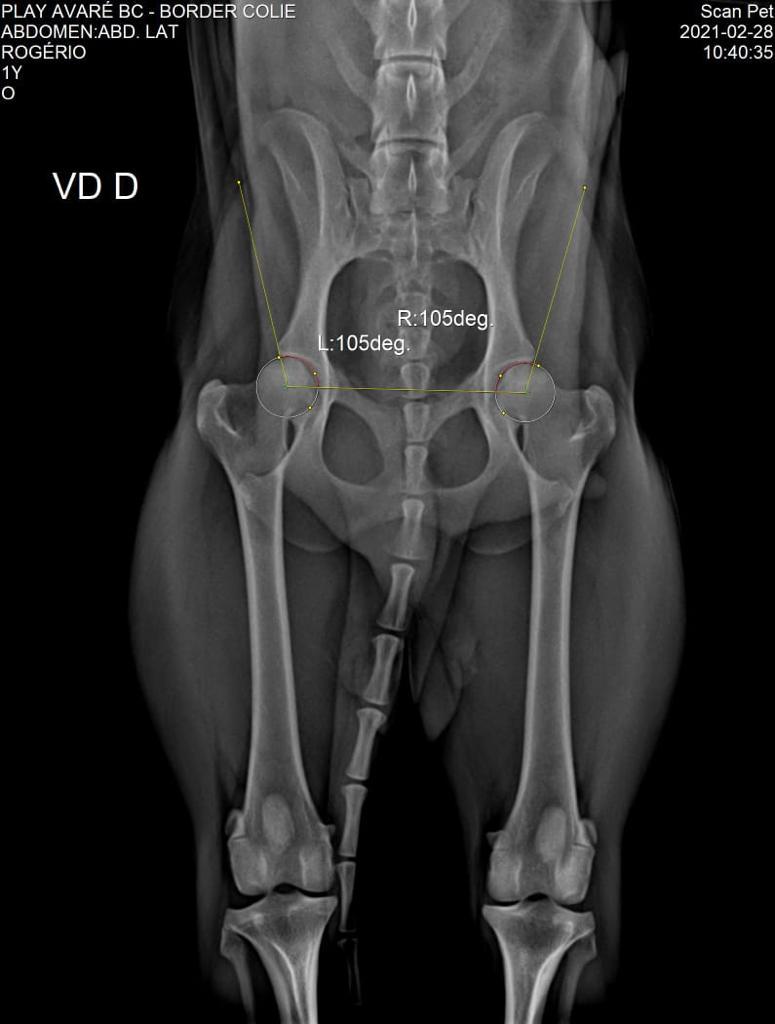

DISPLASIA

07/03/2021

ADEQUADO GRAU A

SCANPET

CHAPA

LAUDO